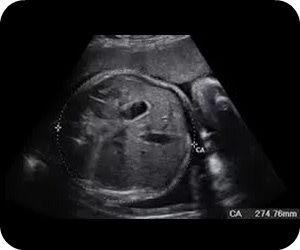

El ultrasonido, conocido como ecografía y ultrasonografía, utiliza ondas sonoras para producir fotografías de las estructuras internas del cuerpo, es un examen de diagnóstico que sirve para visualizar en tiempo real cualquier órgano o tejido del cuerpo, ayuda a examinar al (feto) en las mujeres embarazadas, ayuda a guiar las biopsias, diagnosticar condiciones del corazón, y evaluar el daño luego de ataque cardíaco. El ultrasonido no es invasivo y no utiliza radiación.